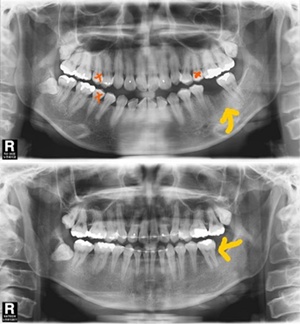

마지막으로는 어금니가 빠진 자리를 치아교정으로 치아를 이동하여 메우는 방법이다. 이 치료방법은 덧니가 심하다든지 아니면 돌출입이 심해 발치 치아교정이 필요한 경우 사용할 수 있다. 통상적으로 치아교정 시 발치가 필요한 경우 소구치 발치를 하지만 만약 어금니가 없는 부위가 있다면 그 빈 공간을 이용하여 치아를 이동할 수 있다.

만약 한부위에 두 개의 치아가 발치 되어있다면 다른 부위에서 뽑은 소구치를 그 부위 자가치아이식을 하여 버리지 않고 사용할 수도 있다. 치아교정으로 발치된 공간을 없앤다면 임플란트나 브리지 보철치료처럼 인공적인 보철물이 아닌 자기 자신의 치아를 사용할 수 있으므로 영구적이라 할 수 있다. 하지만 치아교정의 경우 뼛속에 있는 치아의 뿌리까지 천천히 이동해 와야 하므로 치료기간이 오래 걸린다는 단점이 있다.